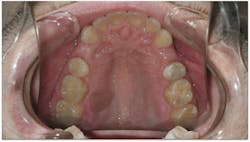

- He measured 28 mm, which is very narrow considering that uncrowded adults measure 35 mm–39 mm.

- His narrow maxilla had a corresponding vaulted palate, which is clearly visible (figure 3).

- He had improper buccolingual inclination as most of the posterior teeth had excess lingual inclination (figure 4).